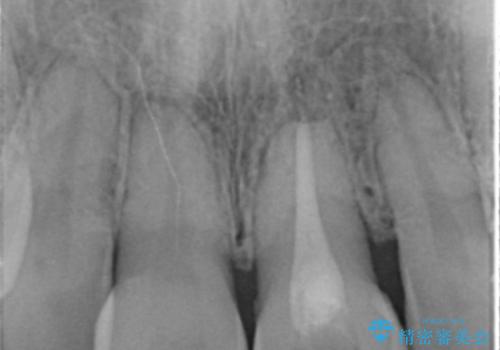

- 神経の治療をしたまま放置していた歯が、変色してきたので改善したい。と前歯の審美性の改善を求めて来院されました。

根管治療後の歯には部分的な修復処置が為され、変色が進行している状態でした。

ジルコニアクラウンを用いて、自然な色調となるよう治療を計画します。